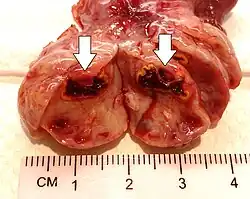

| Corpus luteum cyst with bleeding. Fresh blood is anechoic (black). A protrusion of coagulated blood (lighter in color) can also be seen in the top of the cyst. | |